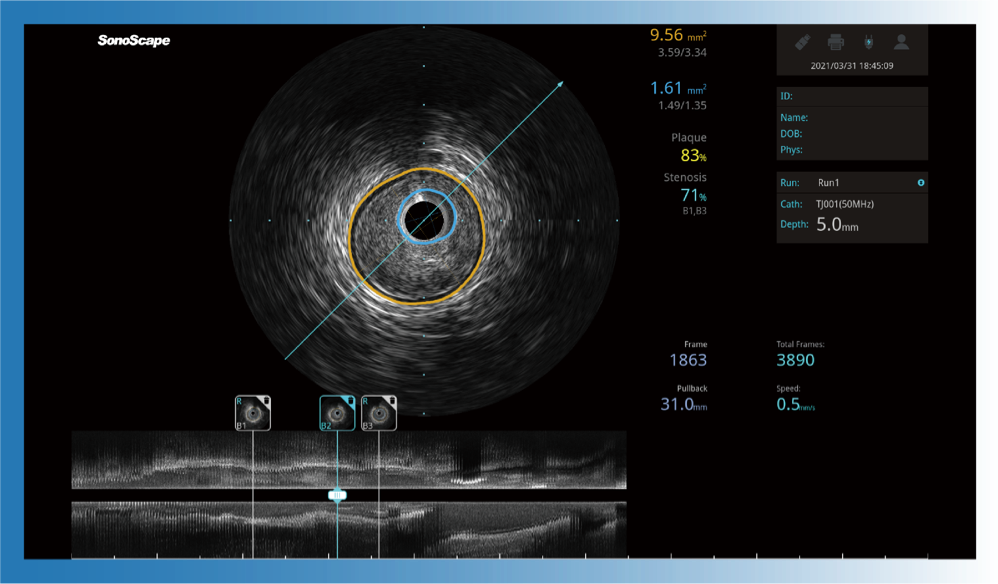

对比传统IVUS导管成像,球速体育入口宽频IVUS图像的近场支架梁显影更细腻,远场中膜外血管仍清晰可辨,兼顾远中近,兼顾分辨力与穿透深度

一键智能描迹,自动测量斑块负荷、面积狭窄率等指标,准确率高于90%